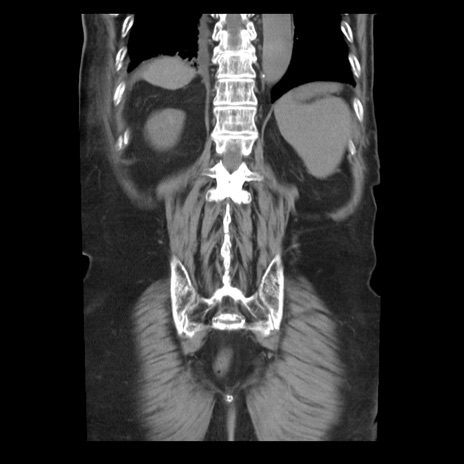

症例21(冠状断像)

【症例】70歳代男性

【主訴】腹痛

【現病歴】肝硬変・肝細胞癌にてかかりつけの方。約9時間前に食後より腹痛出現。症状が徐々に増悪し、嘔吐出現したため来院。

【既往歴】肝硬変、肝細胞癌(RFA、TACE後)

【身体所見】意識清明、表情苦悶様、BT 36℃、BP 129/78mmHg、P 88bpm、SpO2 97%(RA)、右上腹部から心窩部にかけて圧痛あり、反跳痛なし、筋性防御あり。

【データ】WBC 5800、CRP 0.16